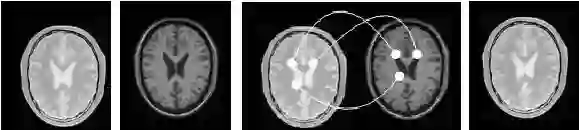

图象配准是图象融合的前提,是公认难度较大的图象处理技术,也是决定医学图象融合技术发展的关键技术。在临床诊断中,单一模态的图像往往不能提供医生所需要的足够信息,常需将多种模式或同一模式的多次成像通过配准融合来实现感兴趣区的信息互补。在一幅图像上同时表达来自多种成像源的信息,医生就能做出更加准确的诊断或制定出更加合适的治疗方法[16]。医学图像配准包括图像的定位和转换,即通过寻找一种空间变换使两幅图像对应点达到空间位置和解剖结构上的完全一致。图6简单说明了二维图像配准的概念。图(a)和图(b)是对应于同一人脑同一位置的两幅 MRI 图像,其中图(a)是质子密度加权成像,图(b)是纵向弛豫加权成像。这两幅图像有明显的不同,第一是方位上的差异,即图(a)相对于图(b)沿水平和垂直方向分别进行了平移;第二是两幅图像所表达的内容是不一致的,图(a)表达不同组织质子含量的差别,而图(b)则突出不同组织纵向弛豫的差别。图(c)给出了两幅图像之间像素点的对应映射关系,即(a)中的每一个点fx都被映射到(b)中唯一的一个点rx。如果这种映射是一一对应的,即一幅图像空间中的每一个点在另外一幅图像空间中都有对应点,或者至少在医疗诊断上感兴趣的那些点能够准确或近似准确的对应起来,我们就称之为配准[17,18]。图(d)给出了图(a)相对于图(b)的配准图像。从图(d)中可以看出,图(d)与(b)之间的的像素点的空间位置已经近似一致了。1993 年 Petra 等综述了二维图像的配准方法,并根据配准基准的特性,将图像配准的方法分为基于外部特征的图象配准(有框架) 和基于图象内部特征的图象配准(无框架) 两种方法。 后者由于其无创性和可回溯性, 已成为配准算法的研究中心。

(a)                 (b)                                (c)                           (d)

图8 医学图像配准原理